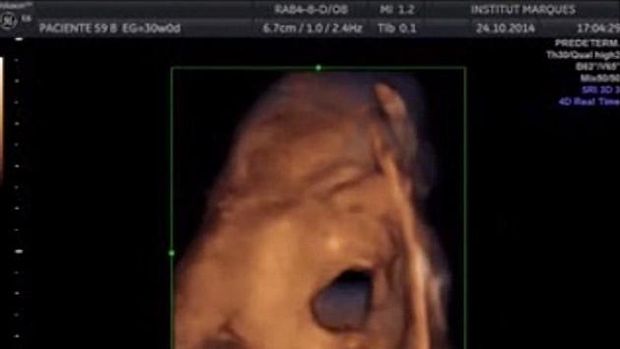

Janin terlihat membuka mulutnya lebar-lebar saat merespons musik (Foto: Institut Marques) |

Namun lewat video yang diunggah lewat situs resmi mereka, terlihat bahwa 87 persen janin bereaksi dengan menggerakkan tangan maupun kepalanya saat diperdengarkan musik. Bahkan beberapa di antaranya tampak melakukan gerakan mulut dan lidah yang spesifik.

50 persen lainnya justru melakukan gerakan yang di luar dugaan, yaitu membuka rahangnya lebar-lebar, dan menjulurkan lidahnya sepanjang mungkin. Peneliti semakin yakin bahwa si bayi berupaya merespons suara yang ia dengar, karena gerakan-gerakan itu otomatis berhenti ketika musik juga berhenti diputar.

Janin terlihat membuka mulutnya lebar-lebar saat merespons musik (Foto: Institut Marques)